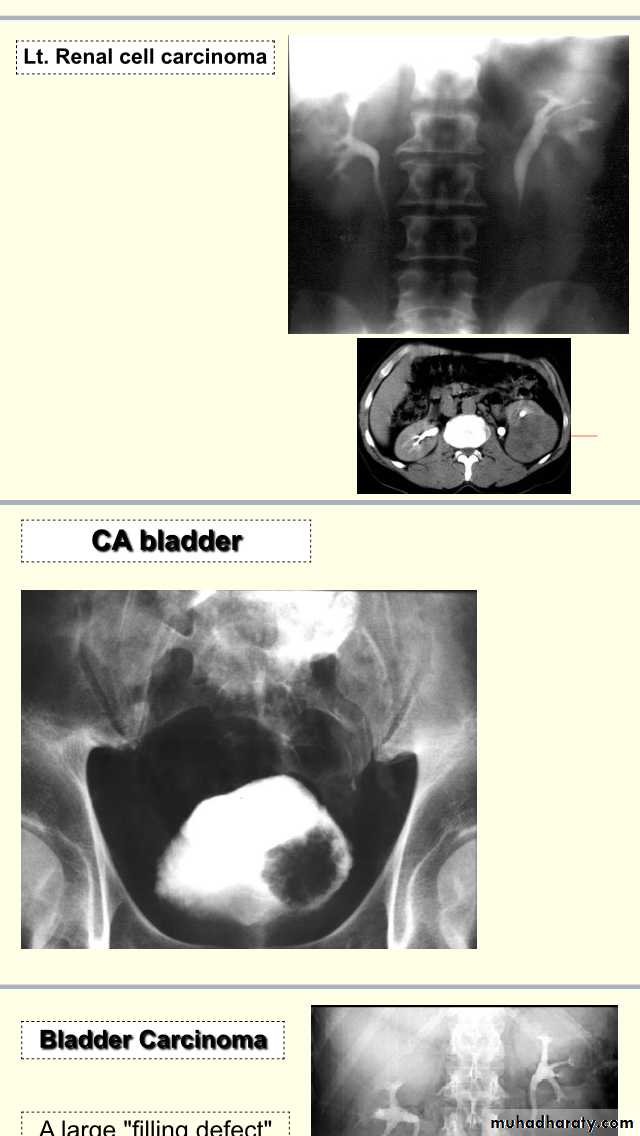

Uroradiology & Slides 1